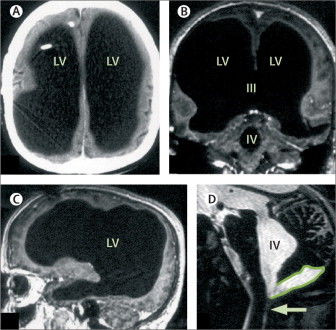

Bệnh nhân người Pháp phải nhập viện sau khi cảm thấy chân trái của mình yếu đi trong hai tuần. Trong quá trình chẩn đoán bệnh, ông được thực hiện nhiều xét nghiệm. Các bác sĩ đã vô cùng ngạc nhiên khi ảnh chụp não của não của bệnh nhân lại không phải não mà là một khoang chứa đầy chất lỏng khổng lồ.

Ảnh chụp não toàn chất lỏng của bệnh nhân

Ảnh chụp não toàn chất lỏng của bệnh nhân.

Thế nhưng kết quả quét não đã khiến tất cả phải giật mình. Não bộ của ông đã sưng lên quá nhiều, chứa đầy dịch tủy, và thứ dịch ấy gần như đã thay thế toàn bộ khối óc, chỉ để lại một lớp vỏ não mỏng chứa các neuron thần kinh. Nói cách khác, người đàn ông này gần như không có não.

Việc chất lỏng lưu thông khắp não là bình thường. Tuy nhiên ở trường hợp này, thay vì được đưa vào hệ thống tuần hoàn, chất lỏng trong não người đàn ông này tích tụ lại. Cuối cùng, sự tích tụ chất lỏng chiếm hết không gian trong sọ, chỉ có một lượng siêu nhỏ là não thực sự.